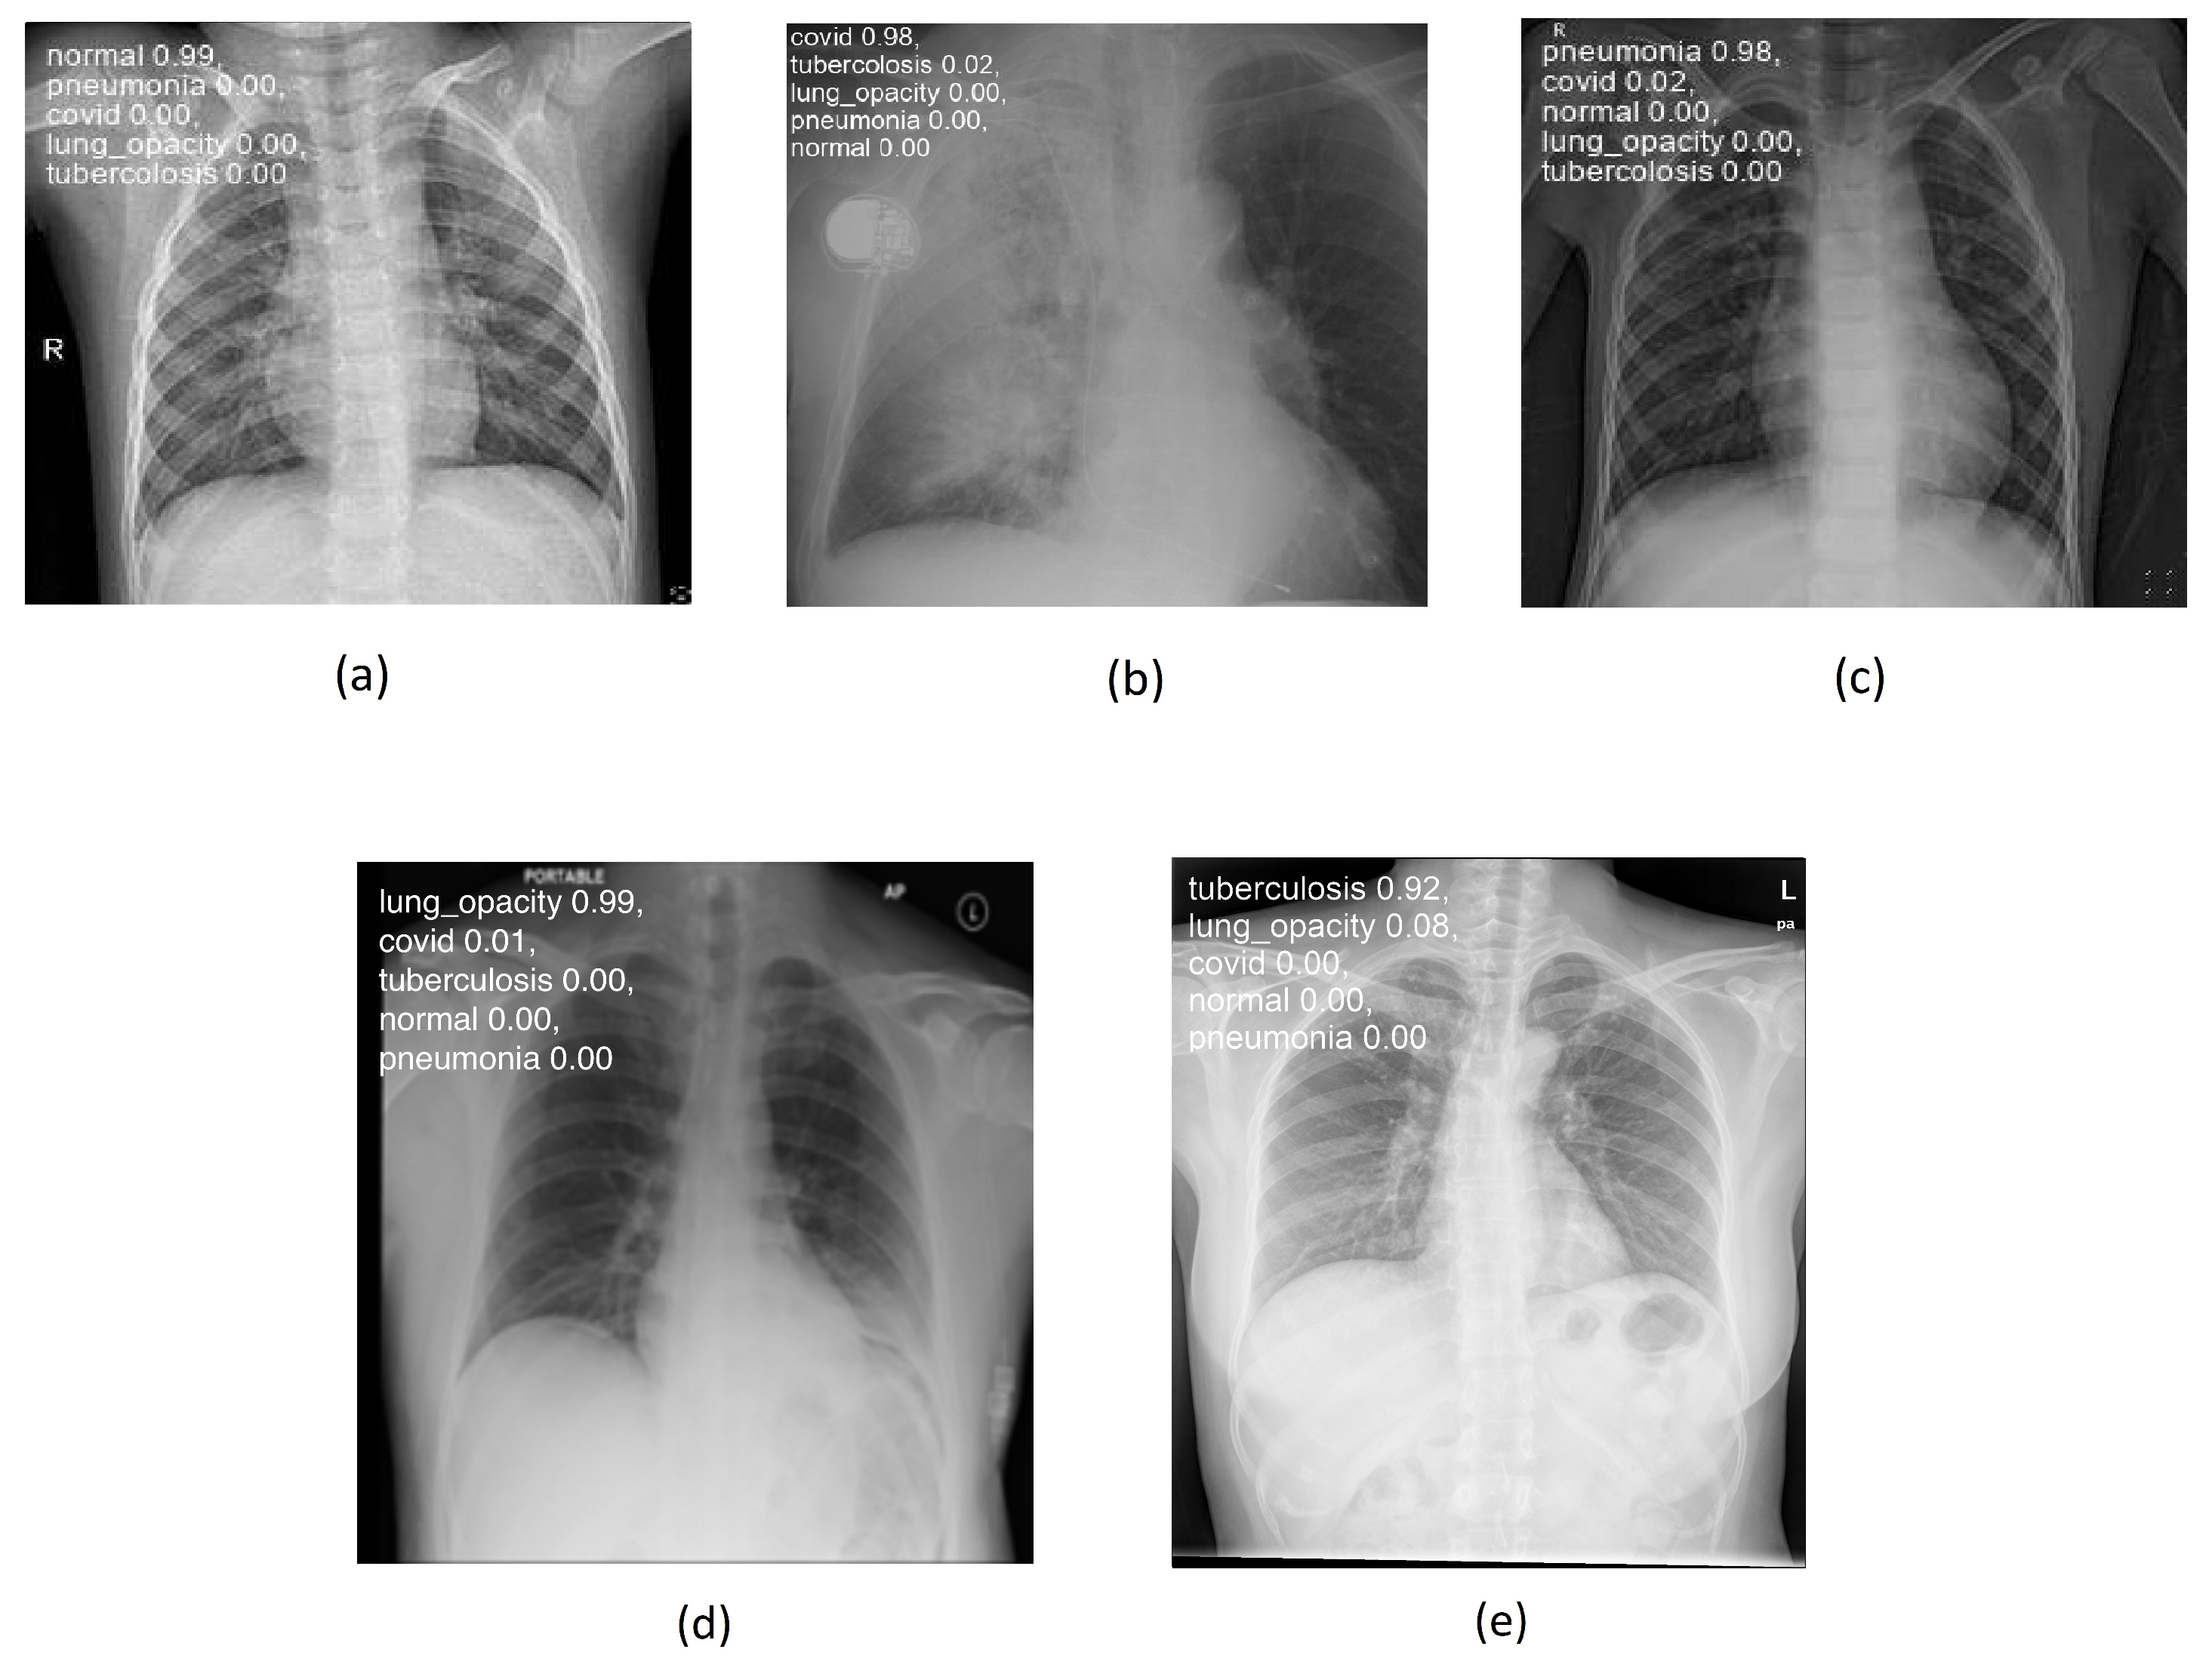

Figure 4a–e below illustrate the “normal”, “covid”, “lung_opacity”, “pneumonia”, and “tuberculosis” classes.

Figure 4. Chest images for (a) “normal”, (b) “covid”, (c) “pneumonia”, (d) “lung_opacity”, and (e) “tuberculosis” classes.